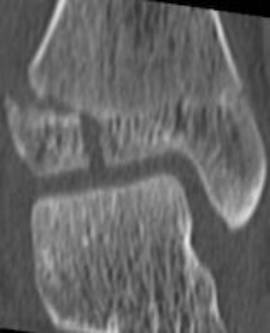

Chance 骨折

胸腰段椎体的分离性骨折,伴随脊髓、神经根、椎体的水平方向的崩裂骨折。